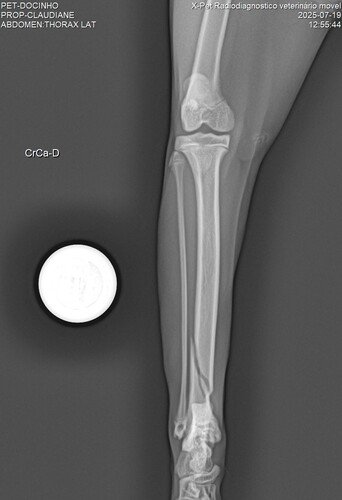

Não podíamos deixa-la na rua, pois ela não resistiria por muito tempo. Então levamos ao veterinário, onde foi feito um Raio X e constatou-se que ela havia fraturado a Tibia e que o tratamento era apenas por meio de uma cirurgia que custava R$ 2.520,00.